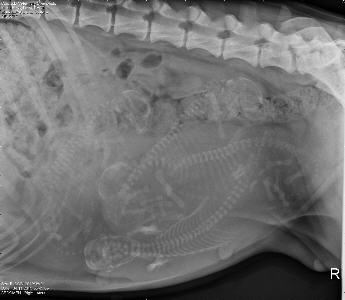

Radiograph image of puppies in womb(Photocredit: Dr. Milan Hess and Veterinary Information Network)

JUST PRIOR TO ISOLATION, IT IS A GOOD IDEA

FOR THE EXPECTANT MOTHER TO HAVE

A RADIOGRAPH OF HER BELLY TO COUNT PUPPIES.

KNOWING HOW MANY PUPPIES TO EXPECT

WILL TELL YOU WHEN SHE IS FINISHED DELIVERING.